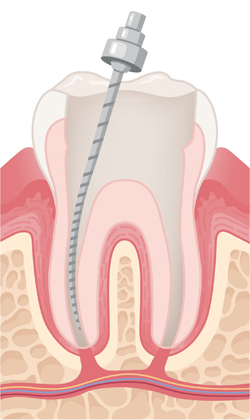

Root canals are filled with a permanent material.

A post is inserted to support the tooth. The opening is sealed with a filling.